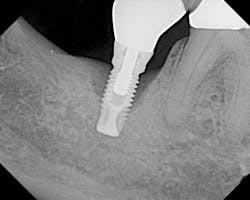

The most critical aspect of any implant system is the interface between the implant fixture and its surrounding bone (figures 1-5). Integration between the fixture and its surrounding bone is the foundation of modern implant dentistry. There is little we can do to modulate bone healing, but we can modify the implant fixture itself.

Figures 1-5: Figures 1 through 4 illustrate, respectively, a seven-year follow-up visit and a three-year follow-up visit of two different implant systems. Implant No. 22 (figure 5) shows peri-implant radiolucency following functional loading, indicating fibroencapsulation and loss of integration into bone, necessitating removal.